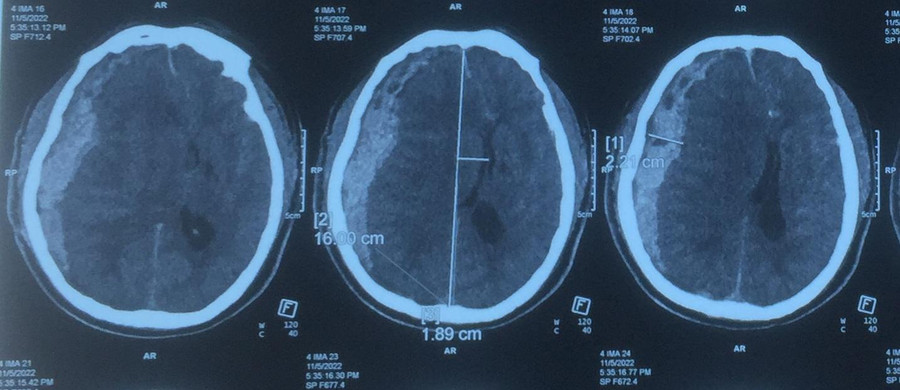

Một trường hợp khác là nam bệnh nhân 67 tuổi. Hai ngày trước vào viện, bệnh nhân sốt cao 39,5 độ C, không điều trị gì. Người nhà phát hiện bệnh nhân trong tình trạng hôn mê, tiểu dầm, được đưa đi cấp cứu tại Bệnh viện Trung ương Quân đội 108 giờ thứ 3 trong tình trạng hôn mê Glasgow 5 điểm, đồng tử mắt phải giãn 5mm.

| Hình ảnh CT sọ não của bệnh nhân: Máu tụ dưới màng cứng bán cầu phải. Ảnh: BV. |

Kết quả chụp CT sọ não có hình ảnh có hình ảnh máu tụ dưới màng cứng bán cầu phải, đè đẩy não thất và đường giữa độ III, test sốt xuất huyết Dengue (+), tiểu cầu 31 G/L, không có khả năng phẫu thuật, bệnh nhân được truyền khối tiểu cầu tách máu, hồi sức tích cực.